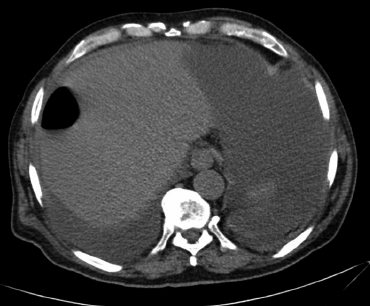

Imágenes y Cirugía

![]() |

Camila Valenzuela Labra, Raúl Valenzuela Labra, Jaime Cruz Fuentes, Matías Orellana Pérez, Marcelo Villarroel Soto, Hernán Valenzuela Valenzuela